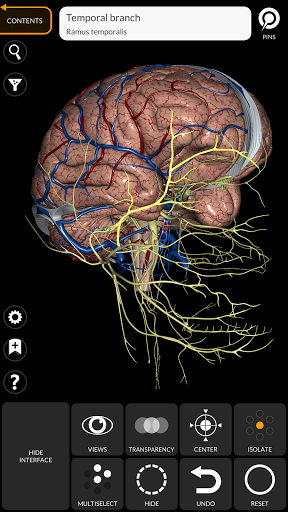

"Anatomy 3D Atlas" memungkinkan Anda mempelajari anatomi manusia dengan cara yang mudah dan interaktif.

Melalui antarmuka yang sederhana dan intuitif, Anda dapat mengamati setiap struktur anatomi dari sudut mana pun.

Model 3D anatomi sangat terperinci dan memiliki tekstur hingga resolusi 4k.

saraf • Sistem pernapasan • Sistem pencernaan • Sistem urogenital (pria dan wanita) • Sistem endokrin • Sistem limfatik • Sistem mata dan telinga FITUR • Antarmuka yang sederhana dan intuitif • Putar dan perbesar setiap model dalam ruang 3D • Opsi untuk menyembunyikan atau mengisolasi satu atau beberapa model yang dipilih • Filter untuk menyembunyikan atau menampilkan setiap sistem • Fungsi pencarian untuk menemukan setiap bagian anatomi dengan mudah • Fungsi penanda untuk menyimpan tampilan khusus • Rotasi cerdas yang menggerakkan pusat rotasi secara otomatis • Fungsi transparansi • Visualisasi otot melalui tingkat lapisan dari yang superfisial hingga yang terdalam • Dengan memilih model atau pin, istilah anatomi terkait akan muncul • Deskripsi otot: asal, • Tampilkan/ Sembunyikan antarmuka UI (sangat berguna dengan layar kecil) MULTIBAHASA • Istilah anatomi dan antarmuka pengguna tersedia dalam 11 bahasa: Latin, Inggris, Prancis, Jerman, Italia, Portugis, Turki, Rusia, Spanyol, Mandarin, Jepang, dan Korea • Istilah anatomi dapat ditampilkan dalam dua bahasa secara bersamaan PERSYARATAN SISTEM • Android 8.0 atau yang lebih baru, perangkat dengan RAM minimal 3GB Reversi

• Sistem saraf